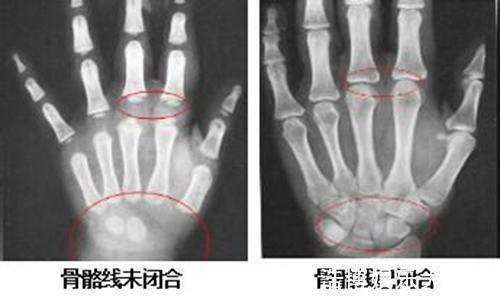

夫妻俩商量着,带孩子去大医院看看,是不是身体缺少什么元素。医院给孩子做了个详细的检查,结果却让芸姐夫妻俩大吃一惊。医生告诉芸姐,孩子这是提前发育了,孩子骨龄已经超过实际年龄好几岁了,骨骼线早已闭合,没有再长高的可能了。